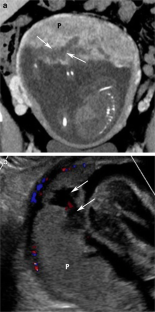

Placental and periplacental bleeding are common etiologies for antepartum bleeding. Placental abruption complicates approximately 1% of pregnancies and is associated with increased maternal, fetal, and neonatal morbidity and mortality. This article reviews the normal placental appearance on ultrasound, computed tomography (CT), and magnetic resonance imaging (MRI) and then discusses the different morphological appearance of placental and periplacental hematomas along with their mimics. Hematomas are classified based on the location as retroplacental, marginal subchorionic, preplacental (subamniotic), or intraplacental. Placenta-related bleeding is a common finding during first trimester ultrasound and its detection can help triage the pregnant females into low- and high-risk groups. This article reviews placenta related bleeding in the setting of trauma. Trauma can complicate pregnancy with potential severe maternal and fetal outcomes. CT is usually performed as part of the trauma workup and it can be challenging for placental evaluation. MRI can characterize the age of the hematomas and can differentiate hematomas from tumors.